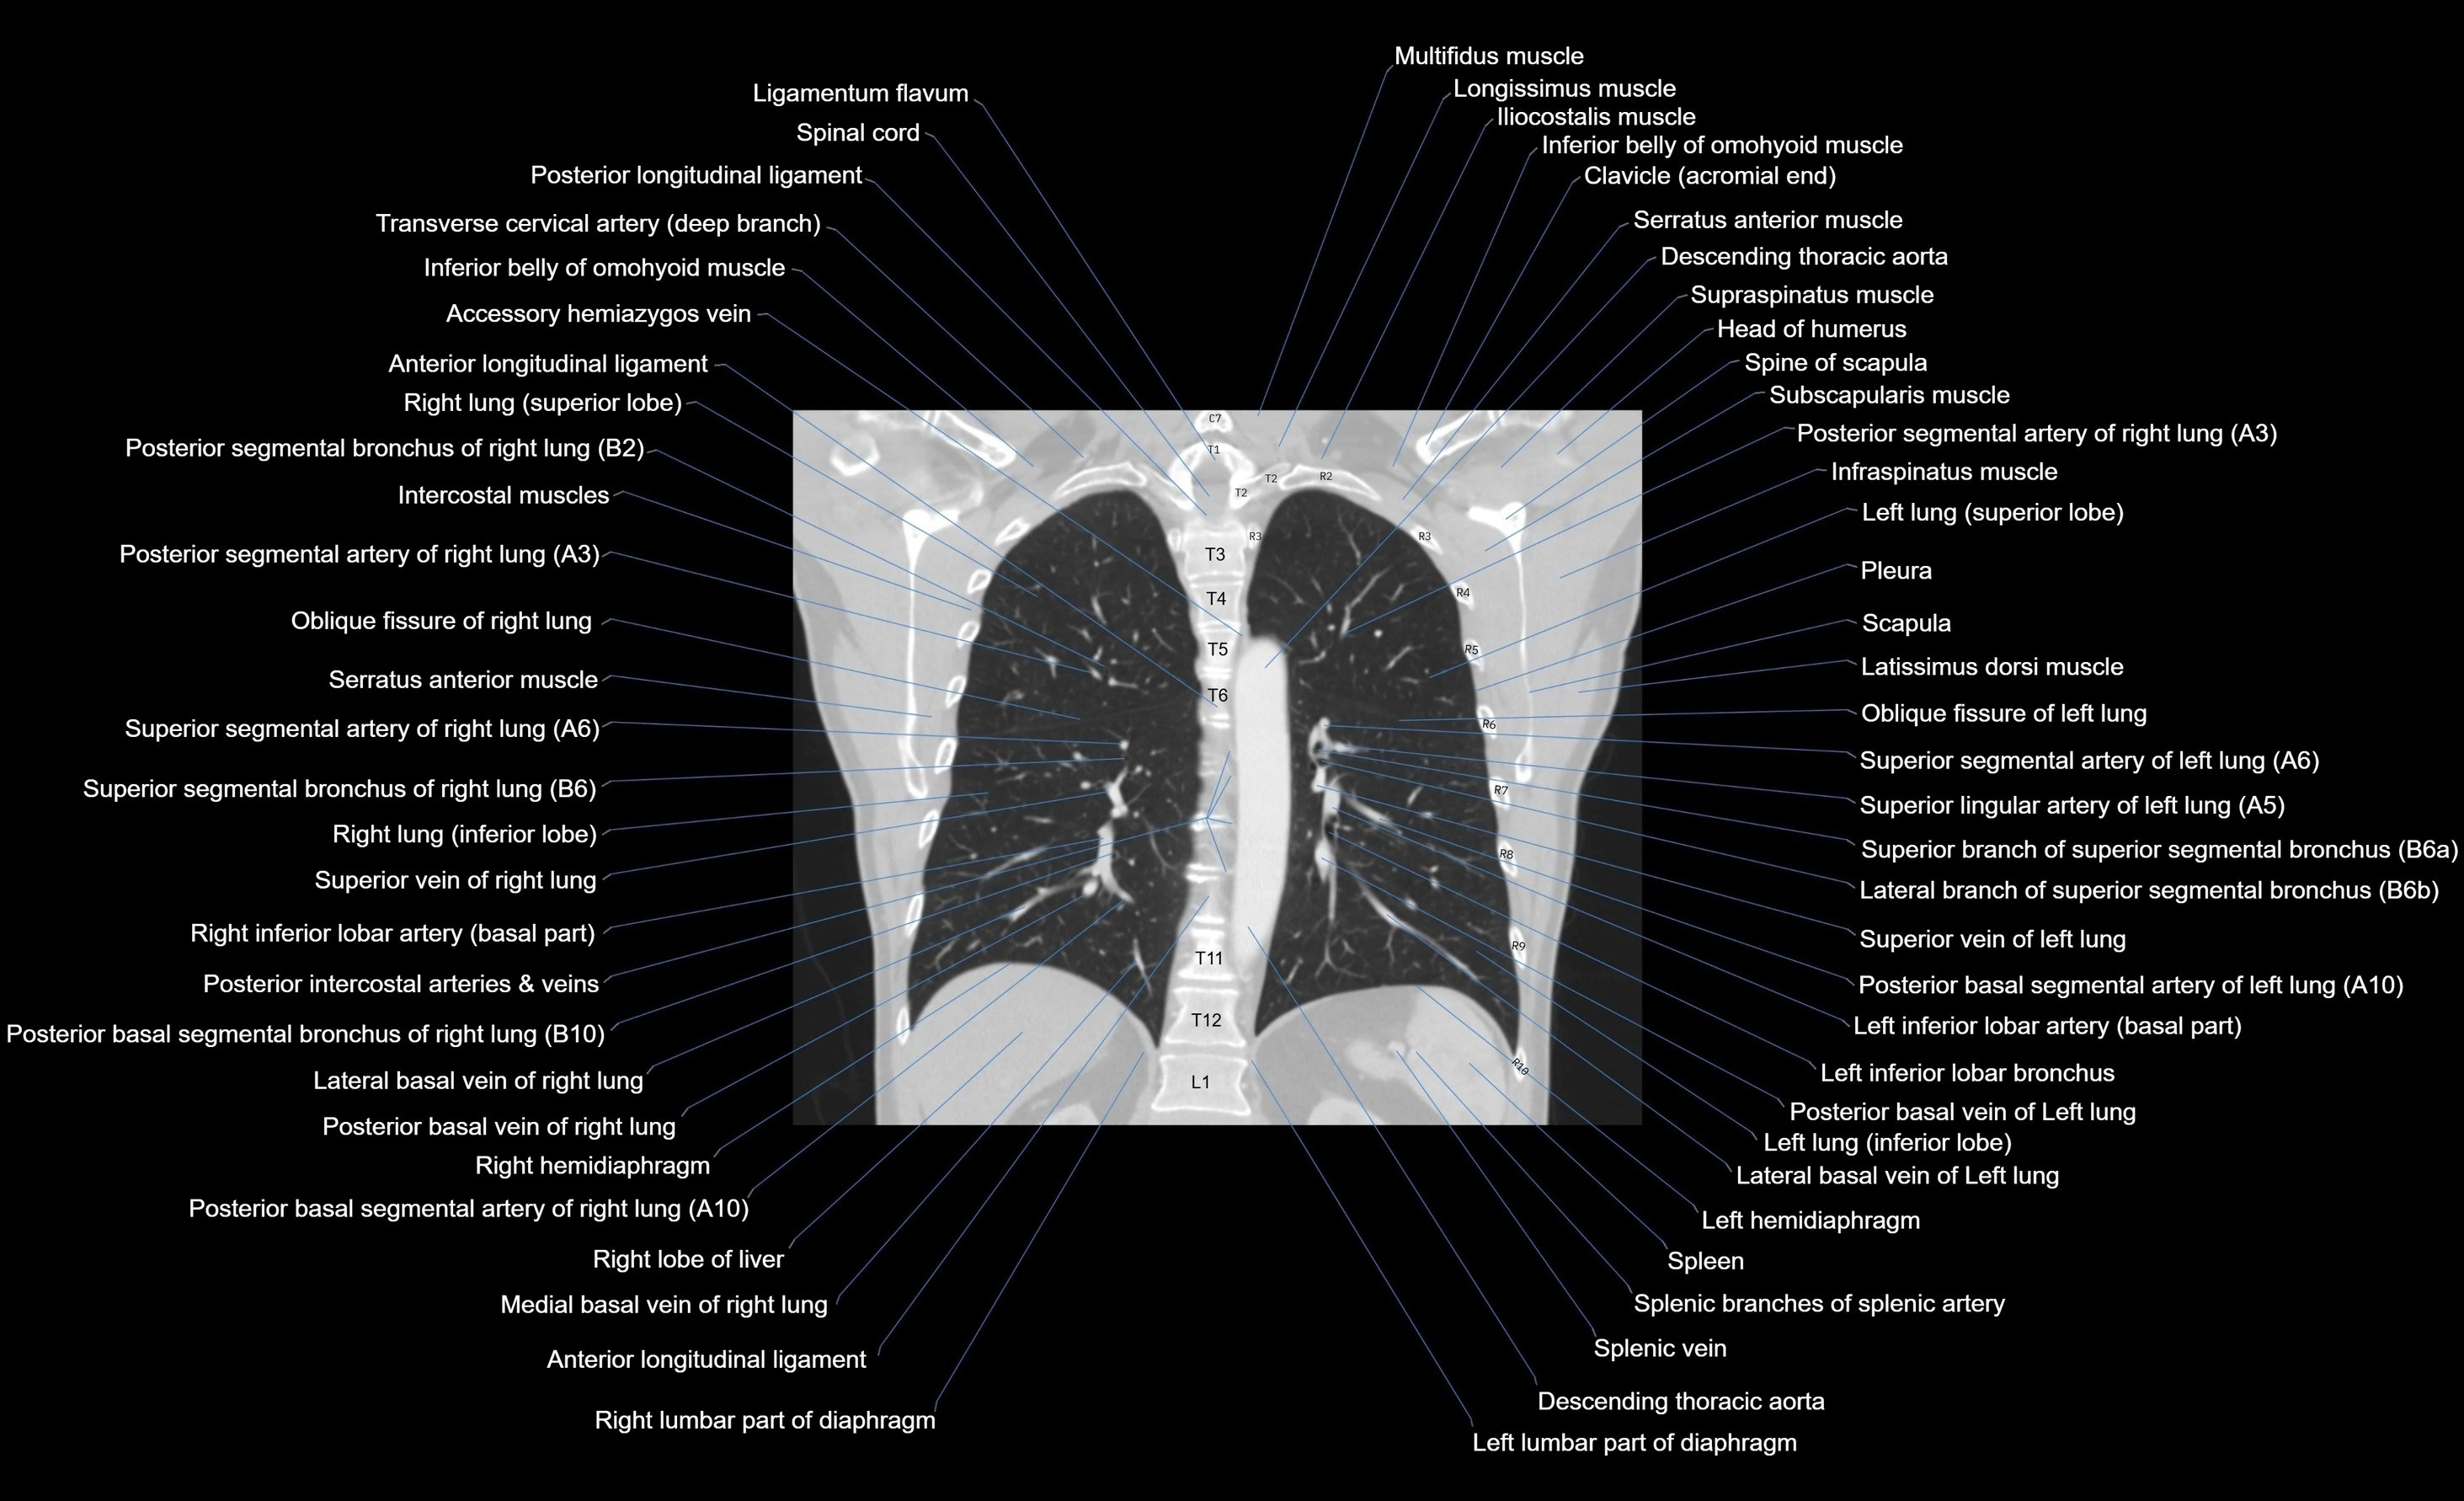

- Descending thoracic aorta

- Left hemidiaphragm

- Right hemidiaphragm

- Right lobe of liver

- Spleen

- Splenic branches of splenic artery

- Splenic vein